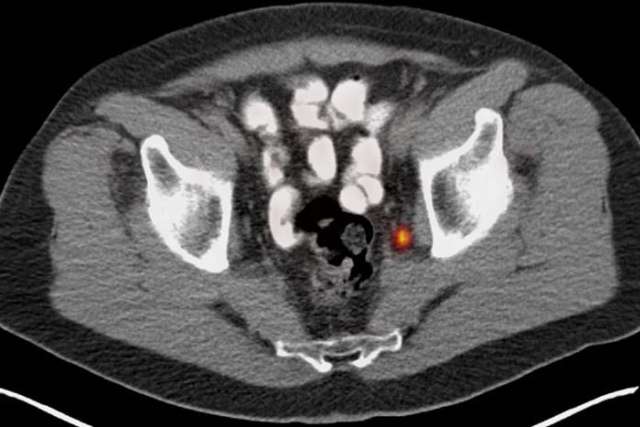

The tool, known as prostate-specific membrane antigen PET imaging, or PSMA PET, provides prognostic information before treatment begins that can predict if the patient will have a high risk for the cancer returning after surgery.

To determine if PSMA PET could improve risk stratification and add value to current tools for determining cancer recurrence before surgery, investigators assessed 240 patients who had PSMA PET prior to surgery.

Each scan was read by three blinded independent readers. PSMA PET and CAPRA scores were then used to assess risk of a biochemical recurrence, which is the reappearance of certain indicators of prostate cancer in the blood (PSA: Prostate Specific Antigen). This occurs in 20-50% of patients within 10 years after surgery. Early biochemical recurrence—happening within three years after surgery—is associated with a poor prognosis and increased cancer-specific mortality.